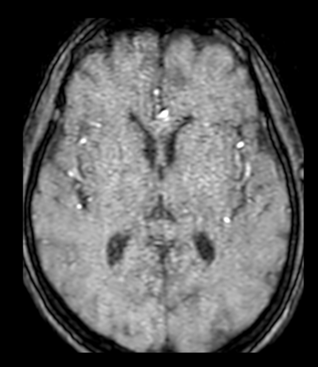

- Cộng hưởng từ sọ não (04/09/2024): Hình ảnh thoái hóa myelin bán cầu hai bên (Fazekas 1). Dày nhẹ niêm mạc xoang sàng.

Hình 4. Chưa phát hiện bất thường.